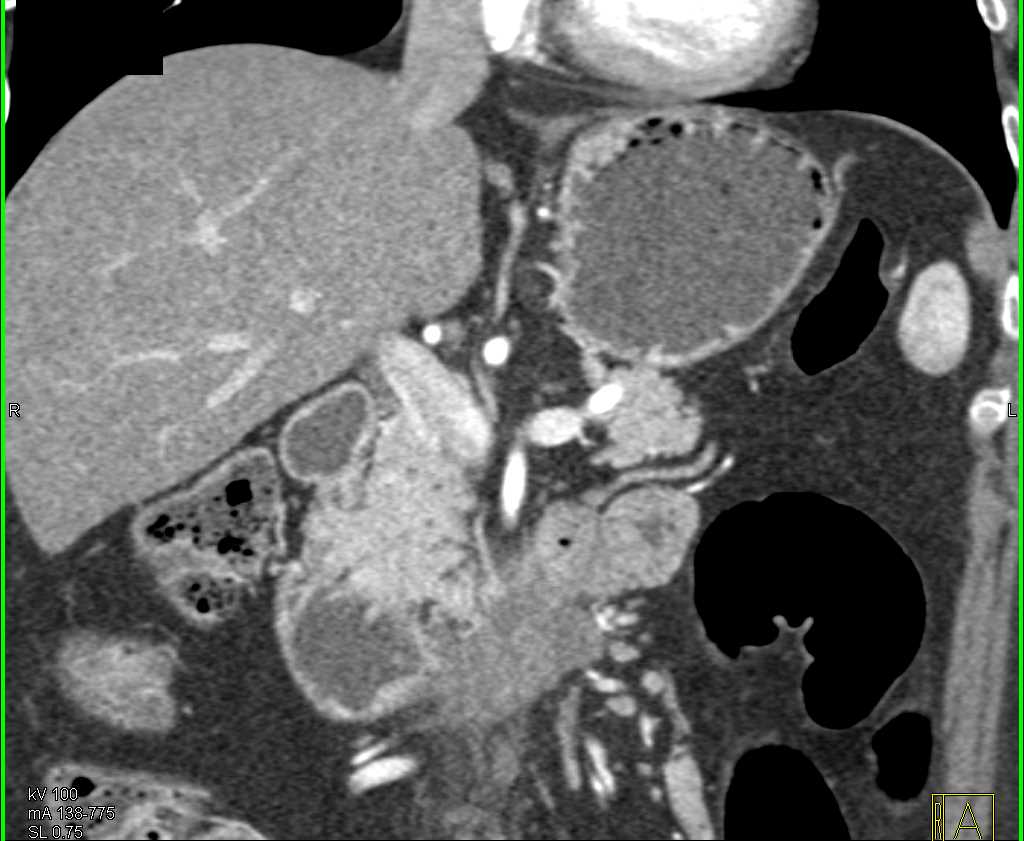

Duodenal Carcinoma with Obstruction